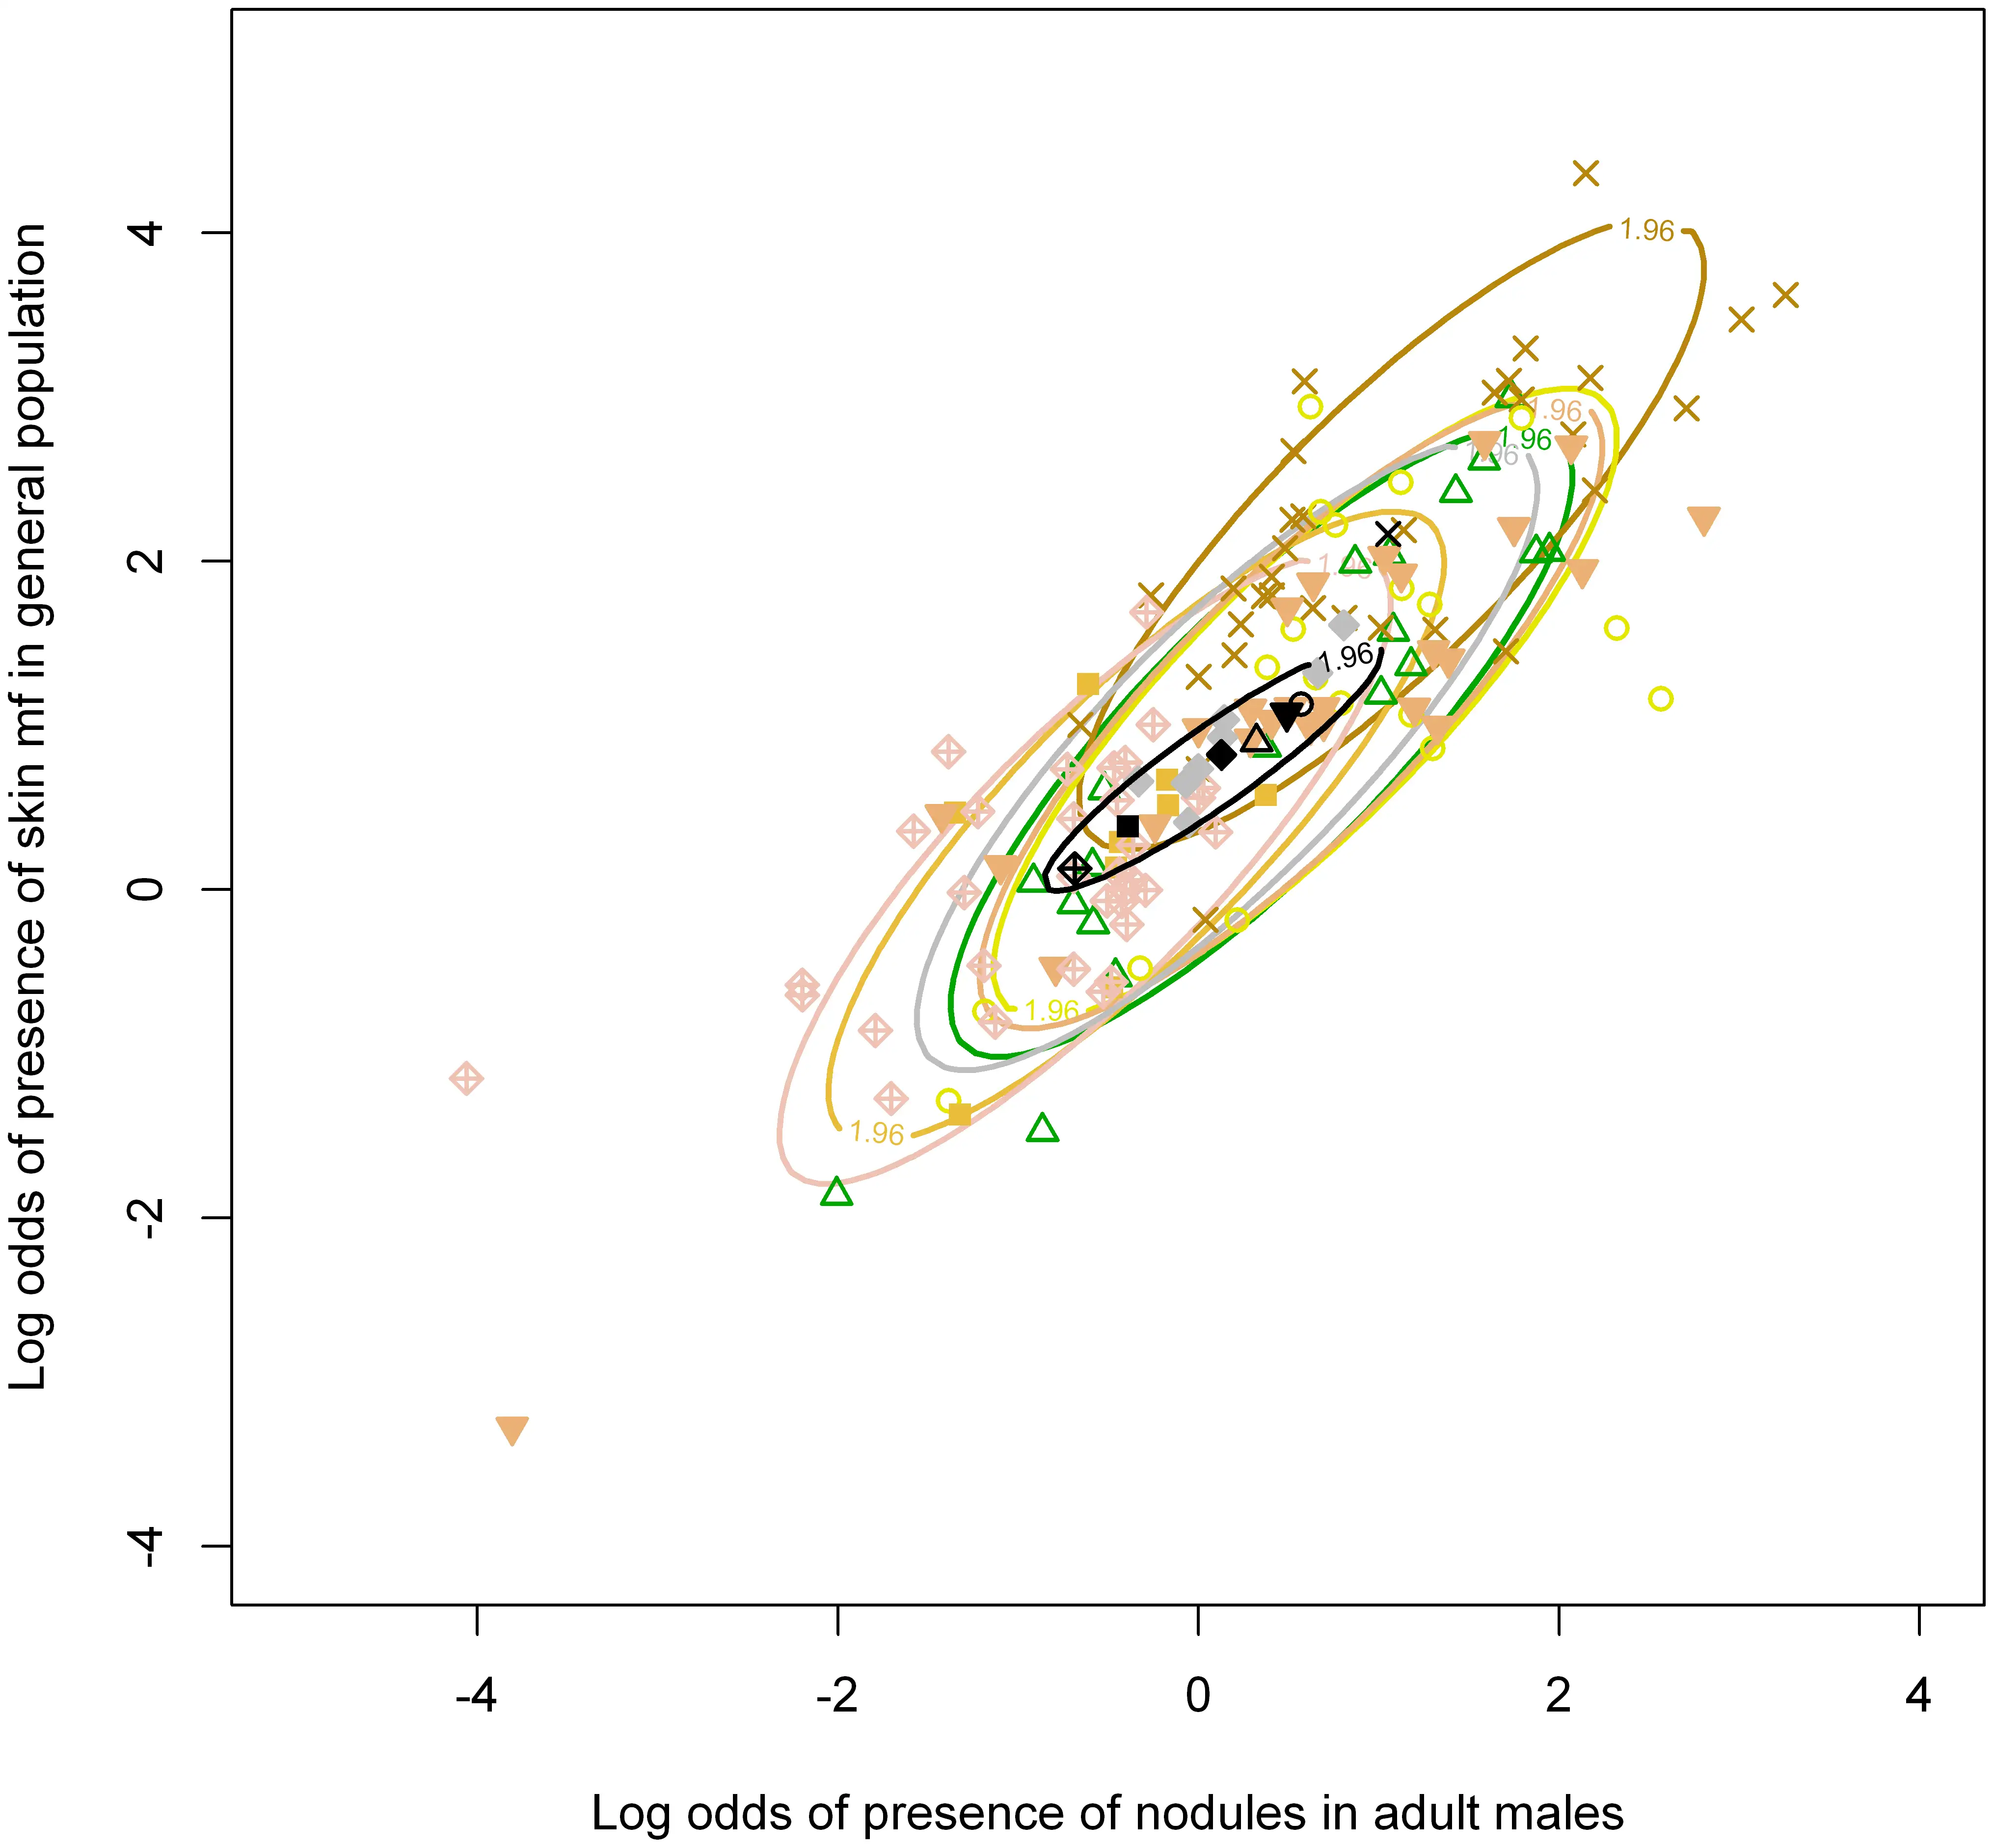

河盲症的眼部病理具有显著的地域差异。在西非的稀树草原地区,眼前段病变更为常见,失明率更高;而在热带雨林地区,后段眼球病变相对多见,但失明率较低。这种差异被认为与不同地区流行的盘尾丝虫株系的毒力差异有关。分子生物学研究证实,稀树草原株系和热带雨林株系在DNA序列上存在可检测的差异,而它们引起的角膜炎症反应也确实不同——稀树草原株系引发更严重的炎症反应。

在非洲,传播河盲症的主要是 Simulium damnosus 复合种群的成员。这是一个包含数十个物种的复杂群体,不同物种在传播效率、叮咬习性和地理分布上各有不同。在西非的热带雨林地区,某些黑蝇物种更倾向于叮咬人类的下半身;而在稀树草原地区,其他物种则更喜欢叮咬躯干和上肢。这些行为差异直接影响着人体感染后微丝蚴在皮肤和眼部的分布模式,也解释了为什么不同地区的河盲症临床表现存在显著差异。